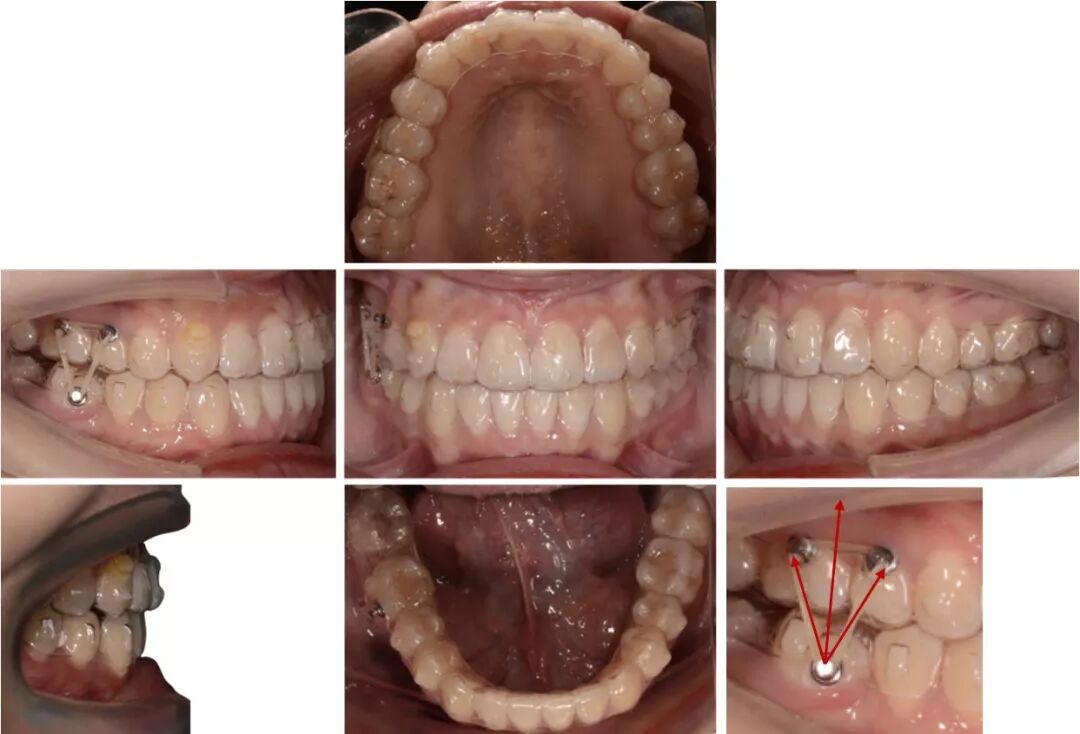

矫治中

第8副,矫治器与牙面贴合,矫治过程中配合III类牵引,有利于尖牙、磨牙关系的改善。

第20副,矫治器与牙面贴合,近中矩形附件使矫治器对47牙有较好的固位,47牙与45相对移动,磨牙尖牙关系改善。

第30副矫治器时,其余牙位矫治器还是比较贴合,但是47牙近中出现了低合与矫治器间隙变大,嘱患者使用咬胶,利用矫治器的力量竖直47牙。

第33副,由于47牙持续的前倾,我们进行了矫治设计的反馈,患者由于干扰的去除,咬合支点的前移,出现了颌位的后退。因为这个原因,实现了比矫治设计更好的尖牙磨牙关系。所以这次我们反馈时提交的是cr位的咬合记录。

第5副,II类牵引来辅助47牙前移,给它部分垂直向分力,但由于水平向上分力更大,使其更前倾,我们停止了长牵引的佩戴。

第30副,改为局部牵引,根据牙齿移动的情况设计牵引,给予其更多的垂直向分力。

第34副矫治器时,48牙近远中和垂直向移动的情况不是太好,我们使用了一个三角形牵引,以矫治器作为引导,帮助它向近中合方移动。